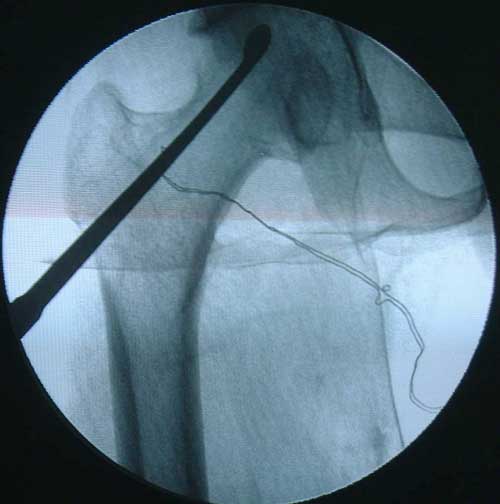

股骨头缺血性坏死MRI显示坏死区                  微创手术方法,采用隧道减压刮除死

BMP植入,异体骨支撑,恢复形态       手术后24个月X线片,关节塌陷未加重,关节功能良好,无疼痛